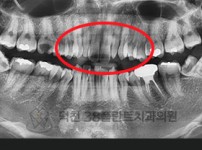

치료전후